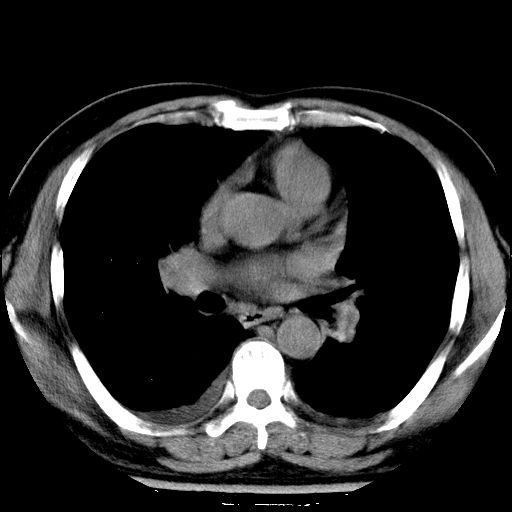

男,65岁,咳嗽、咳痰、发热5天。

慢支 肺间质纤维化合并感染!

支气管扩张合并感染,胸膜肥厚

考虑慢支并感染,肺间质纤维化。

两肺间质性炎症并感染

慢支,肺心病

支持慢性支气管炎伴感染,双侧少量胸腔积液.

两肺间质纤维化,支扩合并感染,双侧胸腔积液

感染,肺间质纤维化。

慢支 肺间质纤维化合并感染

支持慢性支气管、肺间质纤维化合并感染。

慢性支气管炎并感染,支扩,双侧少量胸腔积液.